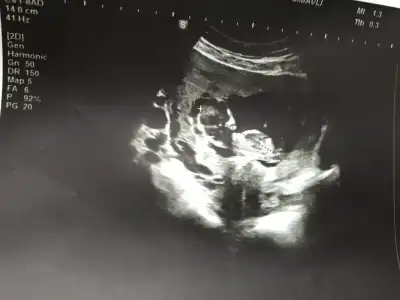

Günaydın Ikra meyra Ikra meyra 1 kızım bir oğlum var bakalım hangisinin yanına eş olcak 😊 11 de ki usg ye de erkek gibi demiştin ben hala anlamıyorum resimlerden bir şey kafa yapısına göre mi yoksa nub a göre mi yorumluyorsun , 1 ay sonra sonraki kontrolüm . Tekrar görürşürüz bakalım sonuçları bildiririm😘

9 haftalık bizi de tahmin eder misiniz

• 20200207_114025.webp

20200207_114025.webp

18 KB · Görüntüleme: 46